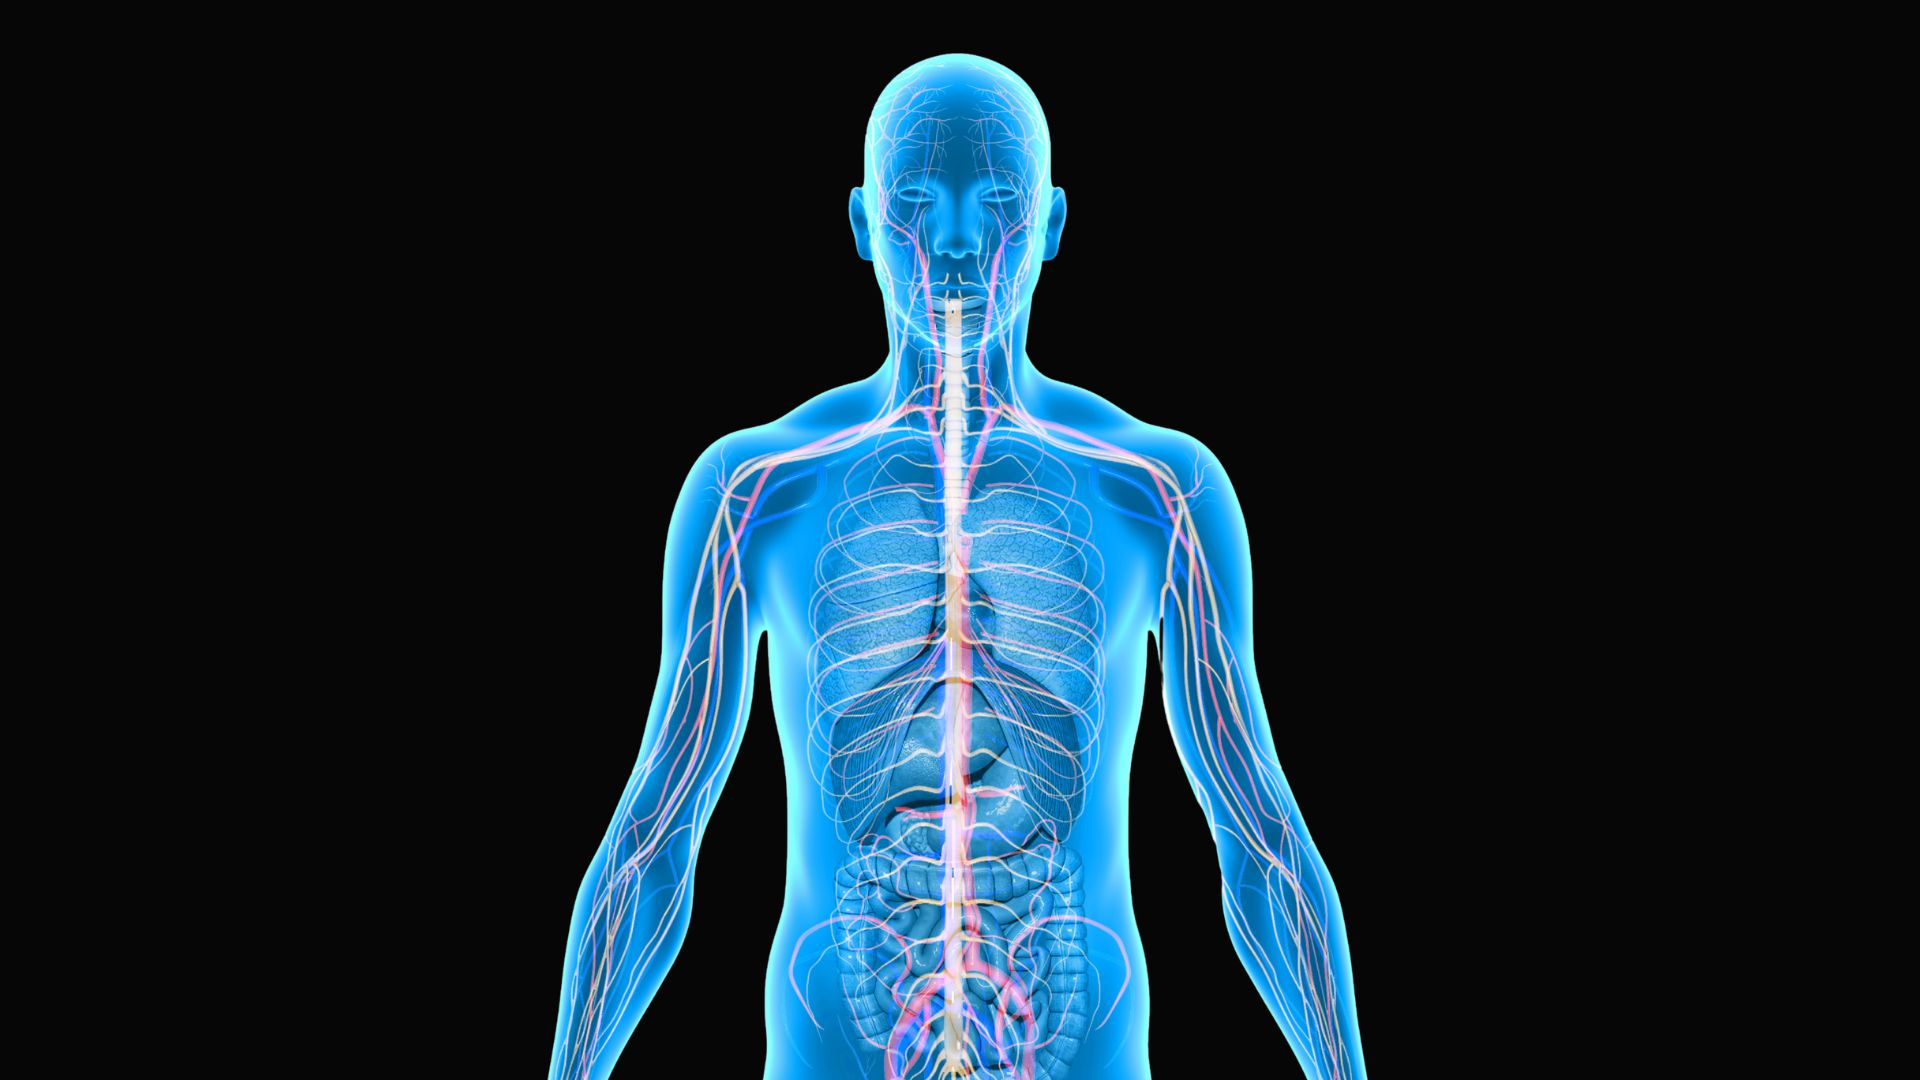

How predictive coding is changing our understanding of the brain

Below is an excellent article by Sage Briggs and here’s a link to a blog that relates to Predictive Coding: https://erikdalton.com/blog/cant-teach-experience-2/ How predictive coding is